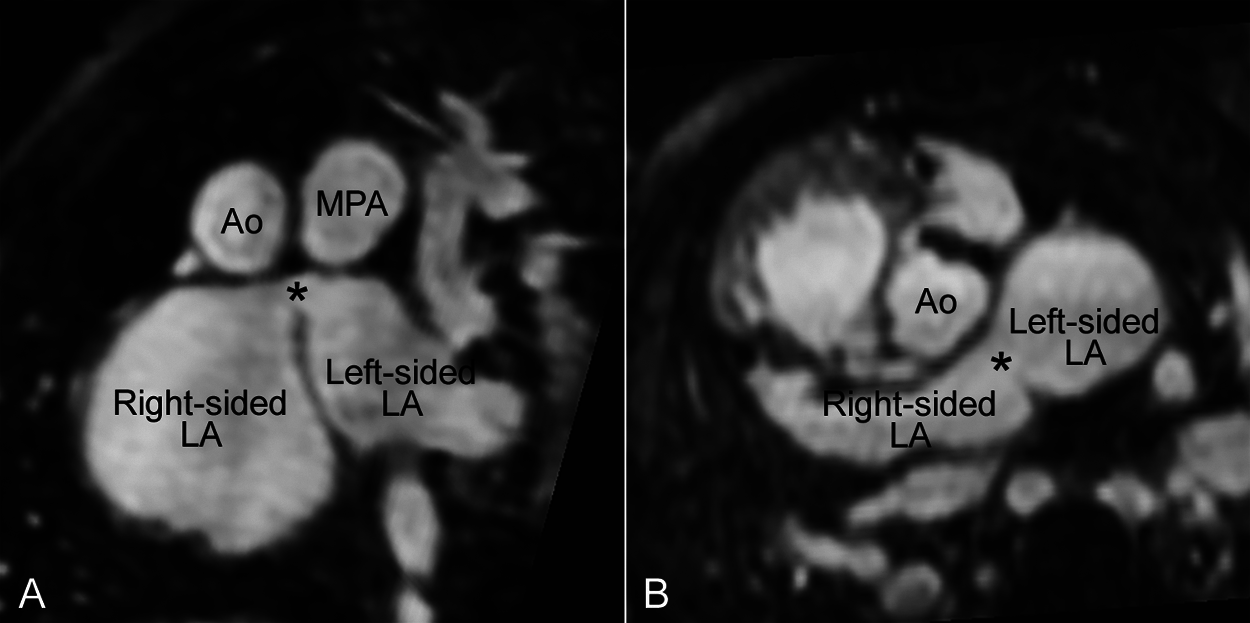

An unusual case with the defect involving the limbus of the fossa ovalis midway between the superior and inferior vena caval orifices in the right atrium was also reported [31]. Cases involving the anteroinferior part of the limbus along the atrioventricular septum have also been described by Keith et al. and later called as atrial septal defects of the septum intermedium or vestibular defects [32–35]. One of the authors (SJY) has experienced a case with heterotaxy and left isomerism of the bronchopulmonary and atrial arrangement that had a small defect in the superior part of the limbus away from the orifices of the right and left superior venae cavae (Fig. 13). A similar case was reported as sinus venosus defect by Talwar et al. without description whether the defect involved the cavoatrial junction [36].

Figure 13: Magnetic resonance angiograms reconstructed in oblique coronal (A) and oblique axial (B) planes showing a defect (asterisk) involving the superior part of the limbus in a patient with heterotaxy and atrial and bronchopulmonary left isomerism. The defect was at distance from the right and left superior vena caval orifices. Ao, aorta; LA, left atrium; MPA, main pulmonary artery